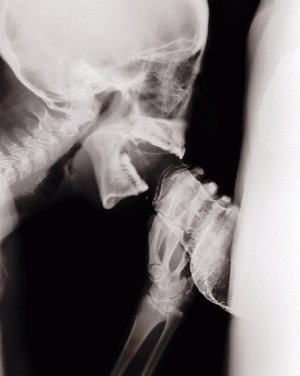

половой акт в разрезе, УЗИ, секс на рентгене

sex x-ray video

секс на томографе MRI

секс изнутри, половой акт в разрезе

как это снимал доктор Pek van Andel